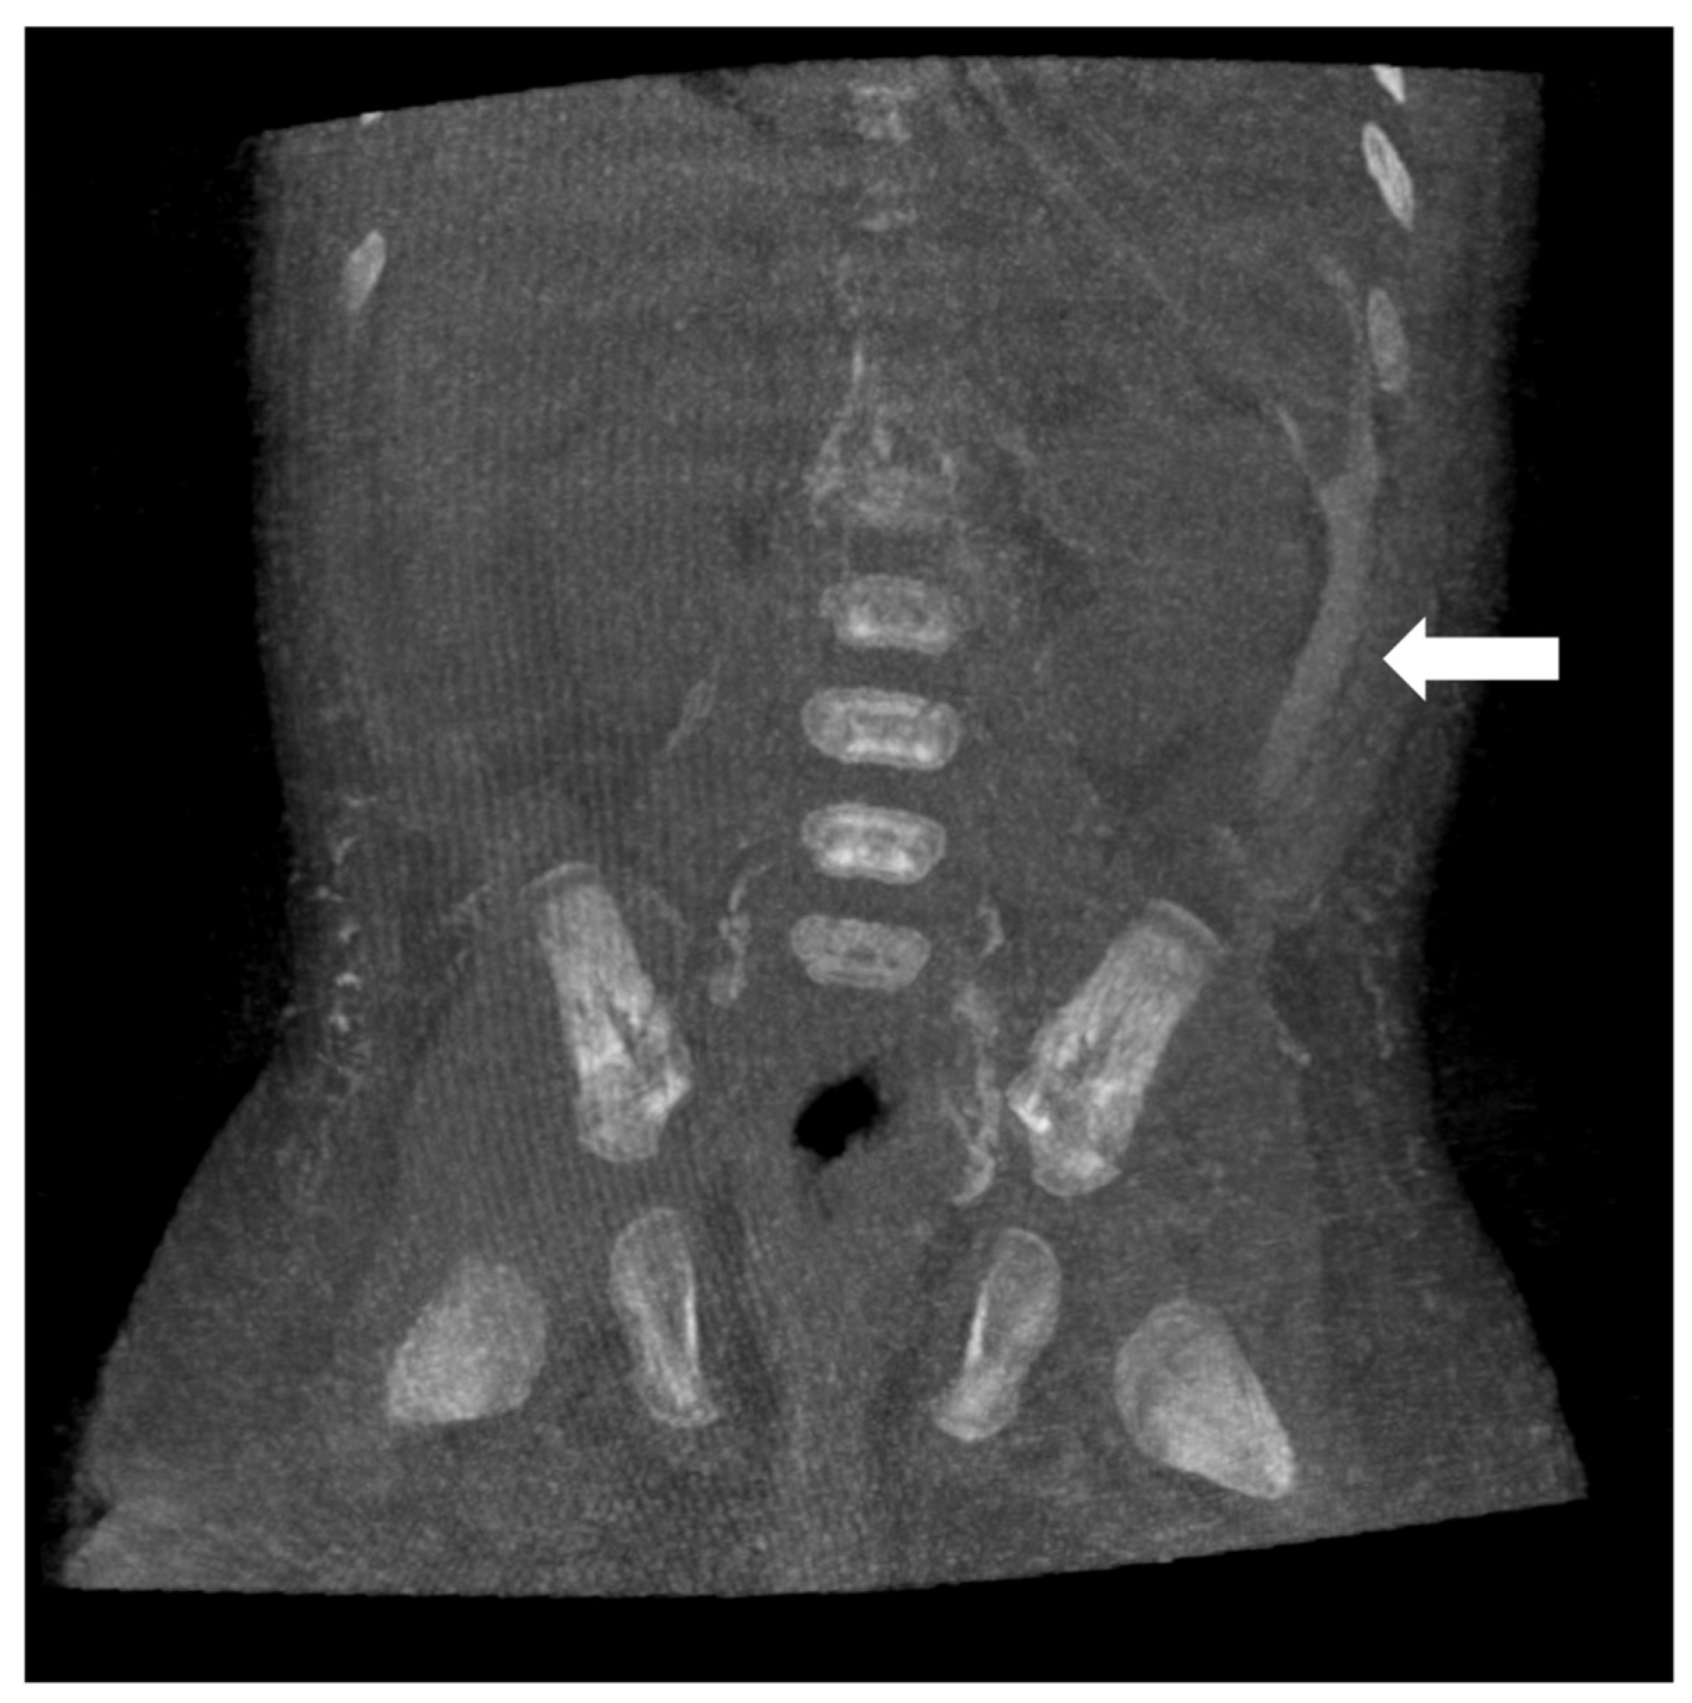

Figure 4. Coronal reformatted image of CBCT of a 56-day-old neonate with diffuse soft tissue edema. Contrast opacification of ascitic fluid (white arrow) confirmed the presence of chylous ascites. This finding was not seen on fluoroscopic images.